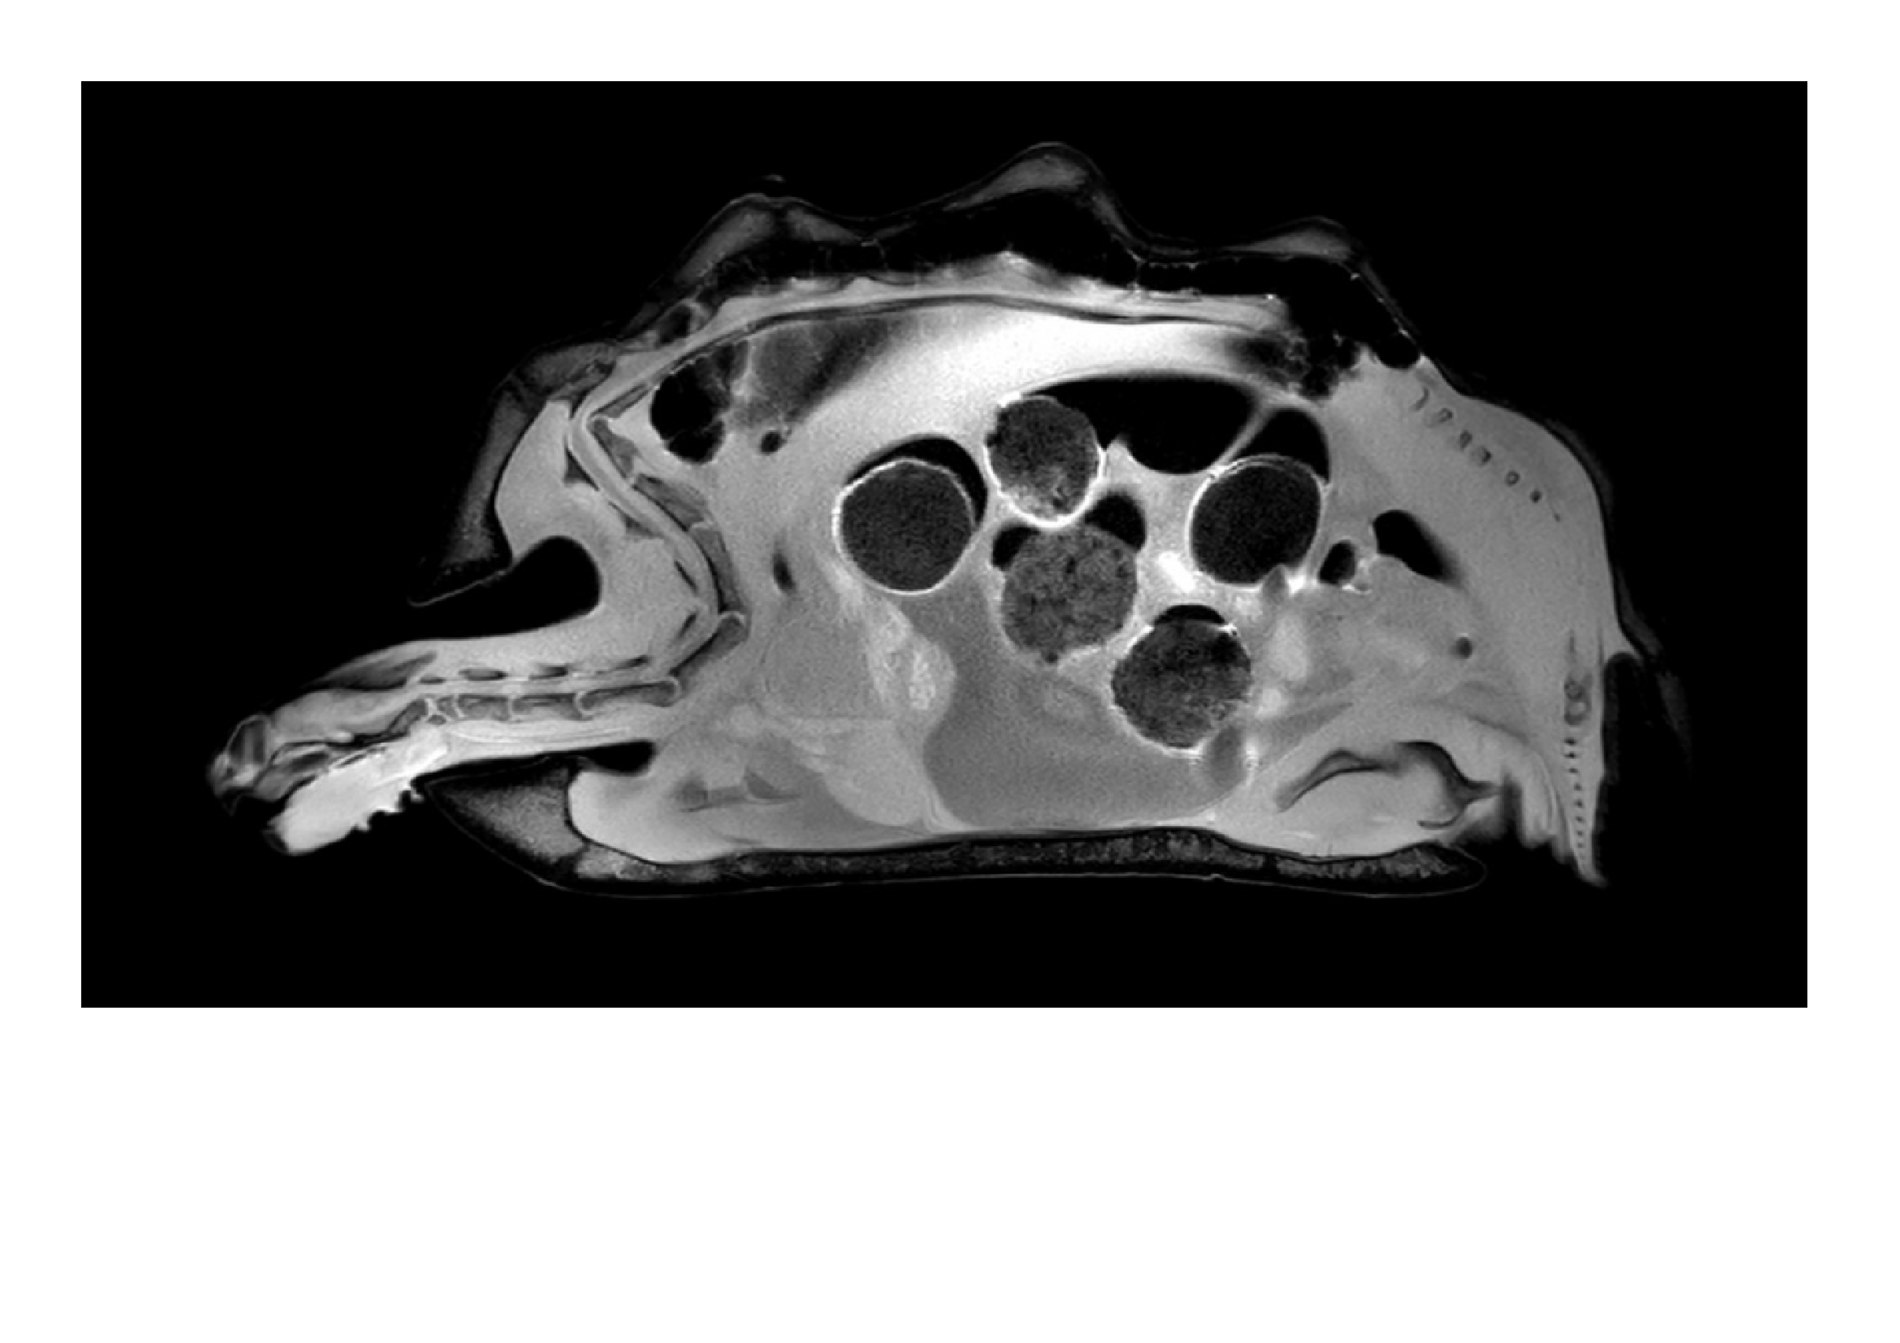

Twój żółw choruje? A może wąż? W Pracowni Rezonansu Magnetycznego Uniwersytetu Przyrodniczego we Wrocławiu badane są nie tylko psy i koty, choć to właśnie one są tu kierowane najczęściej. Pacjentami bywają tu nawet dzikie borsuki oraz lwy, pingwiny i inne zwierzęta z ogrodów zoologicznych.

Pracownia Rezonansu Magnetycznego w Katedrze i Klinice Chirurgii Wydziału Medycyny Weterynaryjnej UPWr specjalizuje się w zaawansowanej diagnostyce obrazowej zwierząt towarzyszących, przede wszystkim psów i kotów. Ale nie tylko, bo coraz częściej pacjentami są tam inne zwierzęta, np żółwie i węże.

Pracownia dysponuje wysokopolowym aparatem Philips Ingenia (1,5T). W ubiegłym roku, po zakupieniu najnowszego oprogramowania, badanie udało się skrócić nawet o 30 procent, co jest szczególnie ważne u starszych zwierząt.